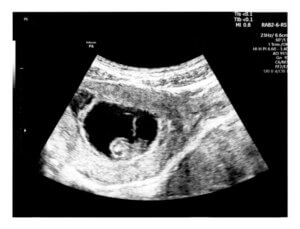

O ultrassom na 6ª semana de gravidez destina-se principalmente a confirmar a viabilidade da gravidez e ouvir os batimentos cardíacos do feto pela primeira vez. Além disso, através das imagens obtidas neste exame, são avaliadas todas as estruturas maternas que se desenvolvem para abrigar a pequena e nova vida.

Todas essas alterações gestacionais podem ser observadas através da ultrassonografia, e a primeira geralmente é feita após a sexta semana de amenorreia. Nesta fase, os primeiros batimentos cardíacos já podem ser percebidos através do ultrassom e, assim, corroboram a viabilidade da gravidez.

Nesta ultrassonografia, é possível observar a presença do embrião e avaliar o estado de saúde dos tecidos maternos. Além disso, com este ultrassom são avaliados os seguintes parâmetros:

- A implantação correta do embrião dentro do endométrio (ou seja, a parede interna do útero). O local em que está localizado e o tamanho da vesícula gestacional, também conhecido como saco gestacional, são determinados.

- O saco gestacional: é uma pequena esfera escura, com uma borda clara, medindo cerca de 8 milímetros neste momento. Dentre suas funções mais importantes, destaca-se a contribuição dos nutrientes necessários ao embrião durante as primeiras semanas. Dentro dessa estrutura, estão a cavidade amniótica, o saco vitelino e o futuro bebê.

- O embrião. Embora ainda muito pequeno para ser visualizado em detalhes, é visto como um espessamento da parede do saco gestacional, próximo ao saco vitelino. Caso não seja possível objetivar naquele momento, o especialista solicitará um novo ultrassom 2 semanas depois.

No primeiro trimestre, a ultrassonografia é realizada por via transvaginal, pois o bebê não é grande o suficiente para ser visualizado pelo abdômen.

Na sexta semana de gestação, o embrião tem de 4 a 5 milímetros de comprimento, por isso é pouco distinguível no ultrassom. No entanto, a formação de seus principais órgãos está avançando.